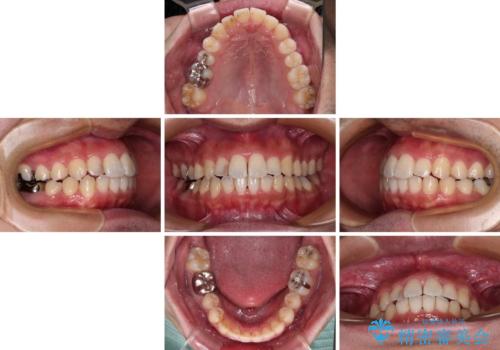

前歯のデコボコと突出感をマウスピース矯正できれいに

- 上下前歯のデコボコと突出感を気にして来院された患者様です。

目立たない装置を希望されたため、インビザラインによるマウスピース矯正を行うこととしました。

矯正治療後に銀歯をセラミックに替えたいとの要望があり、概ね歯列が整ったところで銀歯をセラミックに替え、仕上げにインビザライン1セットを使用して最終的に歯列を整えました。